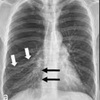

57

Dx

Derrame pleural

58